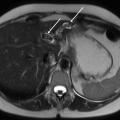

Échographie hépatique : examen clé du diagnostic

L’échographie hépatique est l’examen clé pour le diagnostic de syndrome LPAC. Celle-ci met typiquement en évidence les signes d’une microlithiase intrahépatique sous la forme d’images en « queue de comète » (échos de répétition liés à la vibration des microcristaux sous le faisceau d’ultrasons), de micro-­spots ou de « boue biliaire » (sludge) le long des canaux intrahépatiques (fig. 1A). Ces signes sont parfois difficilement identifiables, notamment en situation non sensibilisée et pour un opérateur non entraîné. Le principal diagnostic différentiel est représenté par les microhamartomes (ou complexes de von Meyenburg) qui peuvent parfois se présenter sous la forme d’artéfacts en queue de comète.9 Une échographie normale standard n’élimine pas le diag­nostic et il peut être nécessaire de répéter l’examen par un radiologue expérimenté et formé à la sémio­logie du syndrome LPAC. Moins fréquemment (5 à 10 % des cas), le syndrome LPAC peut se présenter sous la forme de vrais calculs (macrolithiases) intra- ou extrahépatiques (fig. 1B).4 Une lithiase vésiculaire n’est observée que chez un tiers des patients atteints de syndrome LPAC.

La cholangiographie par IRM est typiquement normale dans les formes habituelles, microlithiasiques, du syndrome LPAC. Elle n’est donc pas nécessaire au diagnostic dans la très grande majorité des situations. Elle doit être réalisée en cas de calculs intrahépatiques ou de dilatation des canaux biliaires en échographie afin d’évaluer le retentissement de ces calculs sur les voies biliaires et le parenchyme hépatique. Les calculs biliaires ne sont pas toujours visibles à l’imagerie par résonance magnétique (IRM), notamment quand leur taille est inférieure à 5 mm. Lorsqu’ils sont visibles, ils sont le plus souvent visualisés en hyposignal T1 et T2 sous forme de lacunes endobiliaires (fig. 2 A et 2B). Dans une série récente portant sur 125 patients suivis dans un centre expert et ayant tous eu une bili-IRM, 49 % présentaient des anomalies des canaux biliaires, parmi lesquelles 93 % de calculs intra­hépatiques et 38 % de dilatation des canaux biliaires.10 Ces anomalies morphologiques étaient plus fréquemment observées chez les porteurs d’un variant pathogène du gène ABCB4.